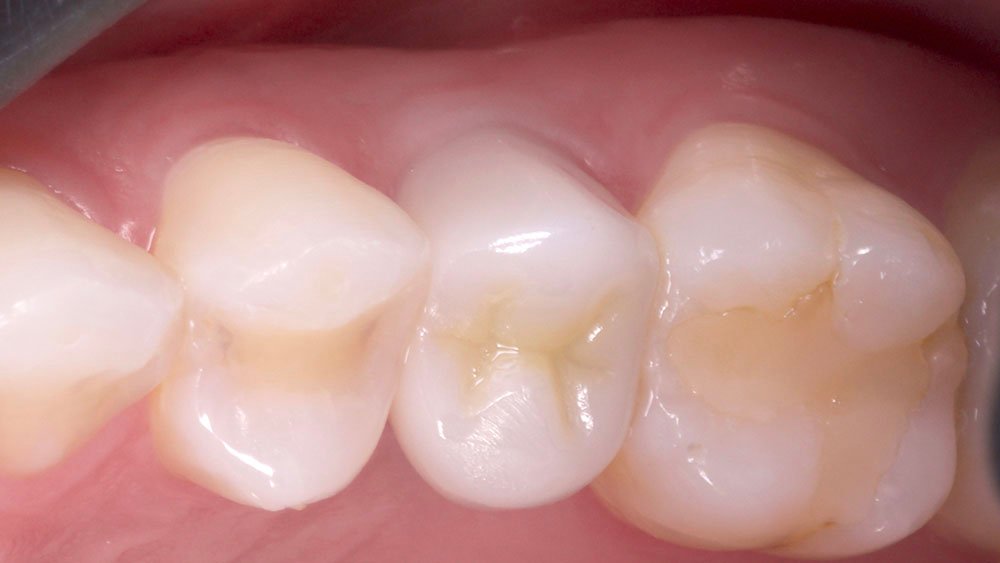

Durante a anamnese, a paciente apresentou um bom estado de saúde geral e não relatou nenhum dado médico relevante que impossibilitasse o tratamento. No exame físico intraoral, observou uma boa condição de saúde bucal, notando-se apenas a ausência do elemento 15 com uma depressão óssea no vestibular. Dessa forma, objetivou-se um plano de tratamento baseado na utilização da técnica de rolo modificada e colocação de dente provisório.

No acompanhamento mensal realizou-se proservação e radiografias periapicais da região para verificar a cicatrização dos tecidos e integridade do implante. Após o período de três meses, foi cimentada uma coroa definitiva de zircônia monolítica.